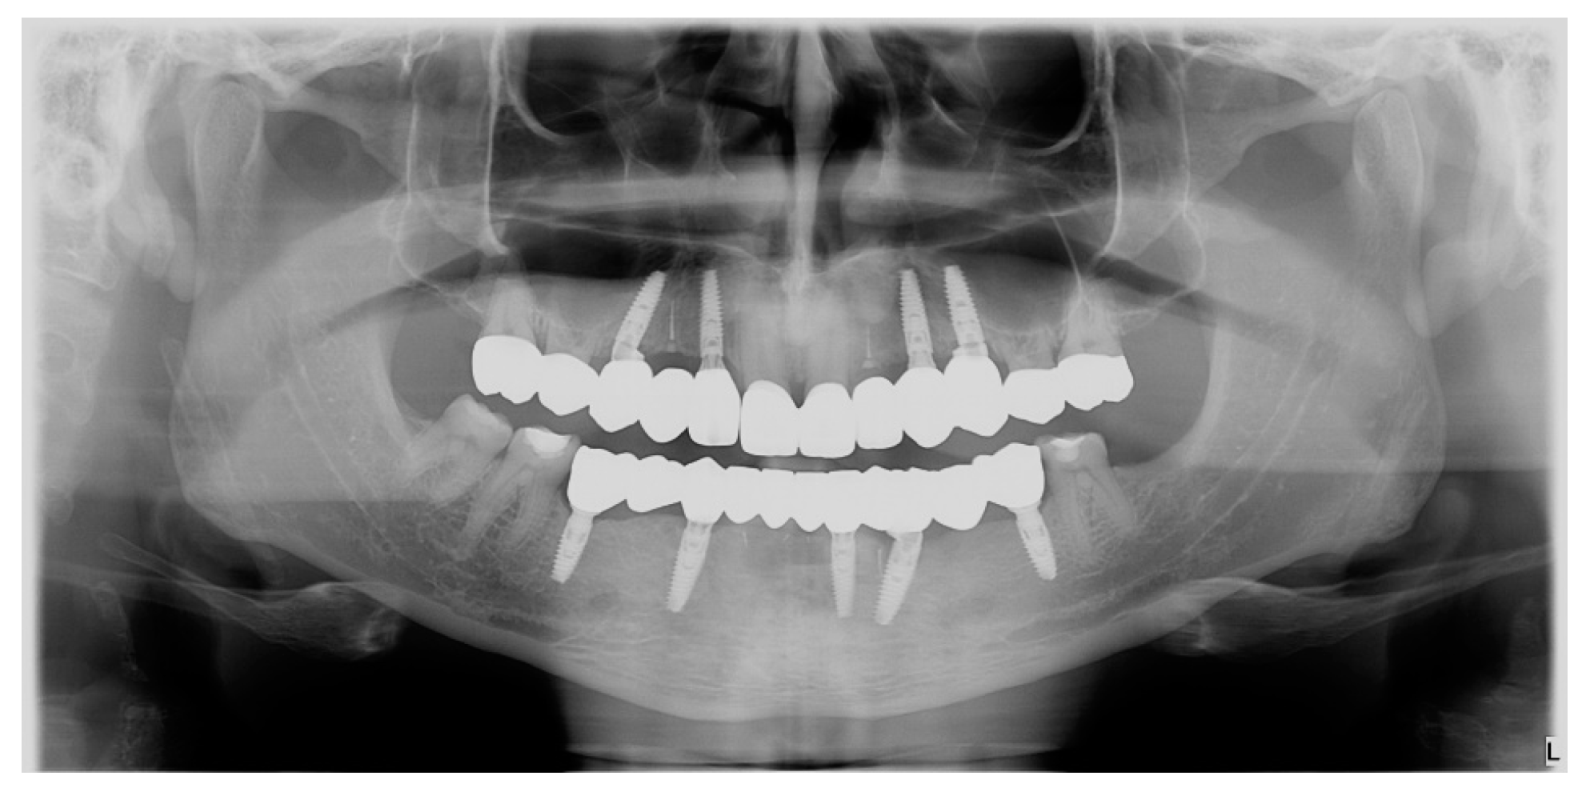

- Final restorations placement